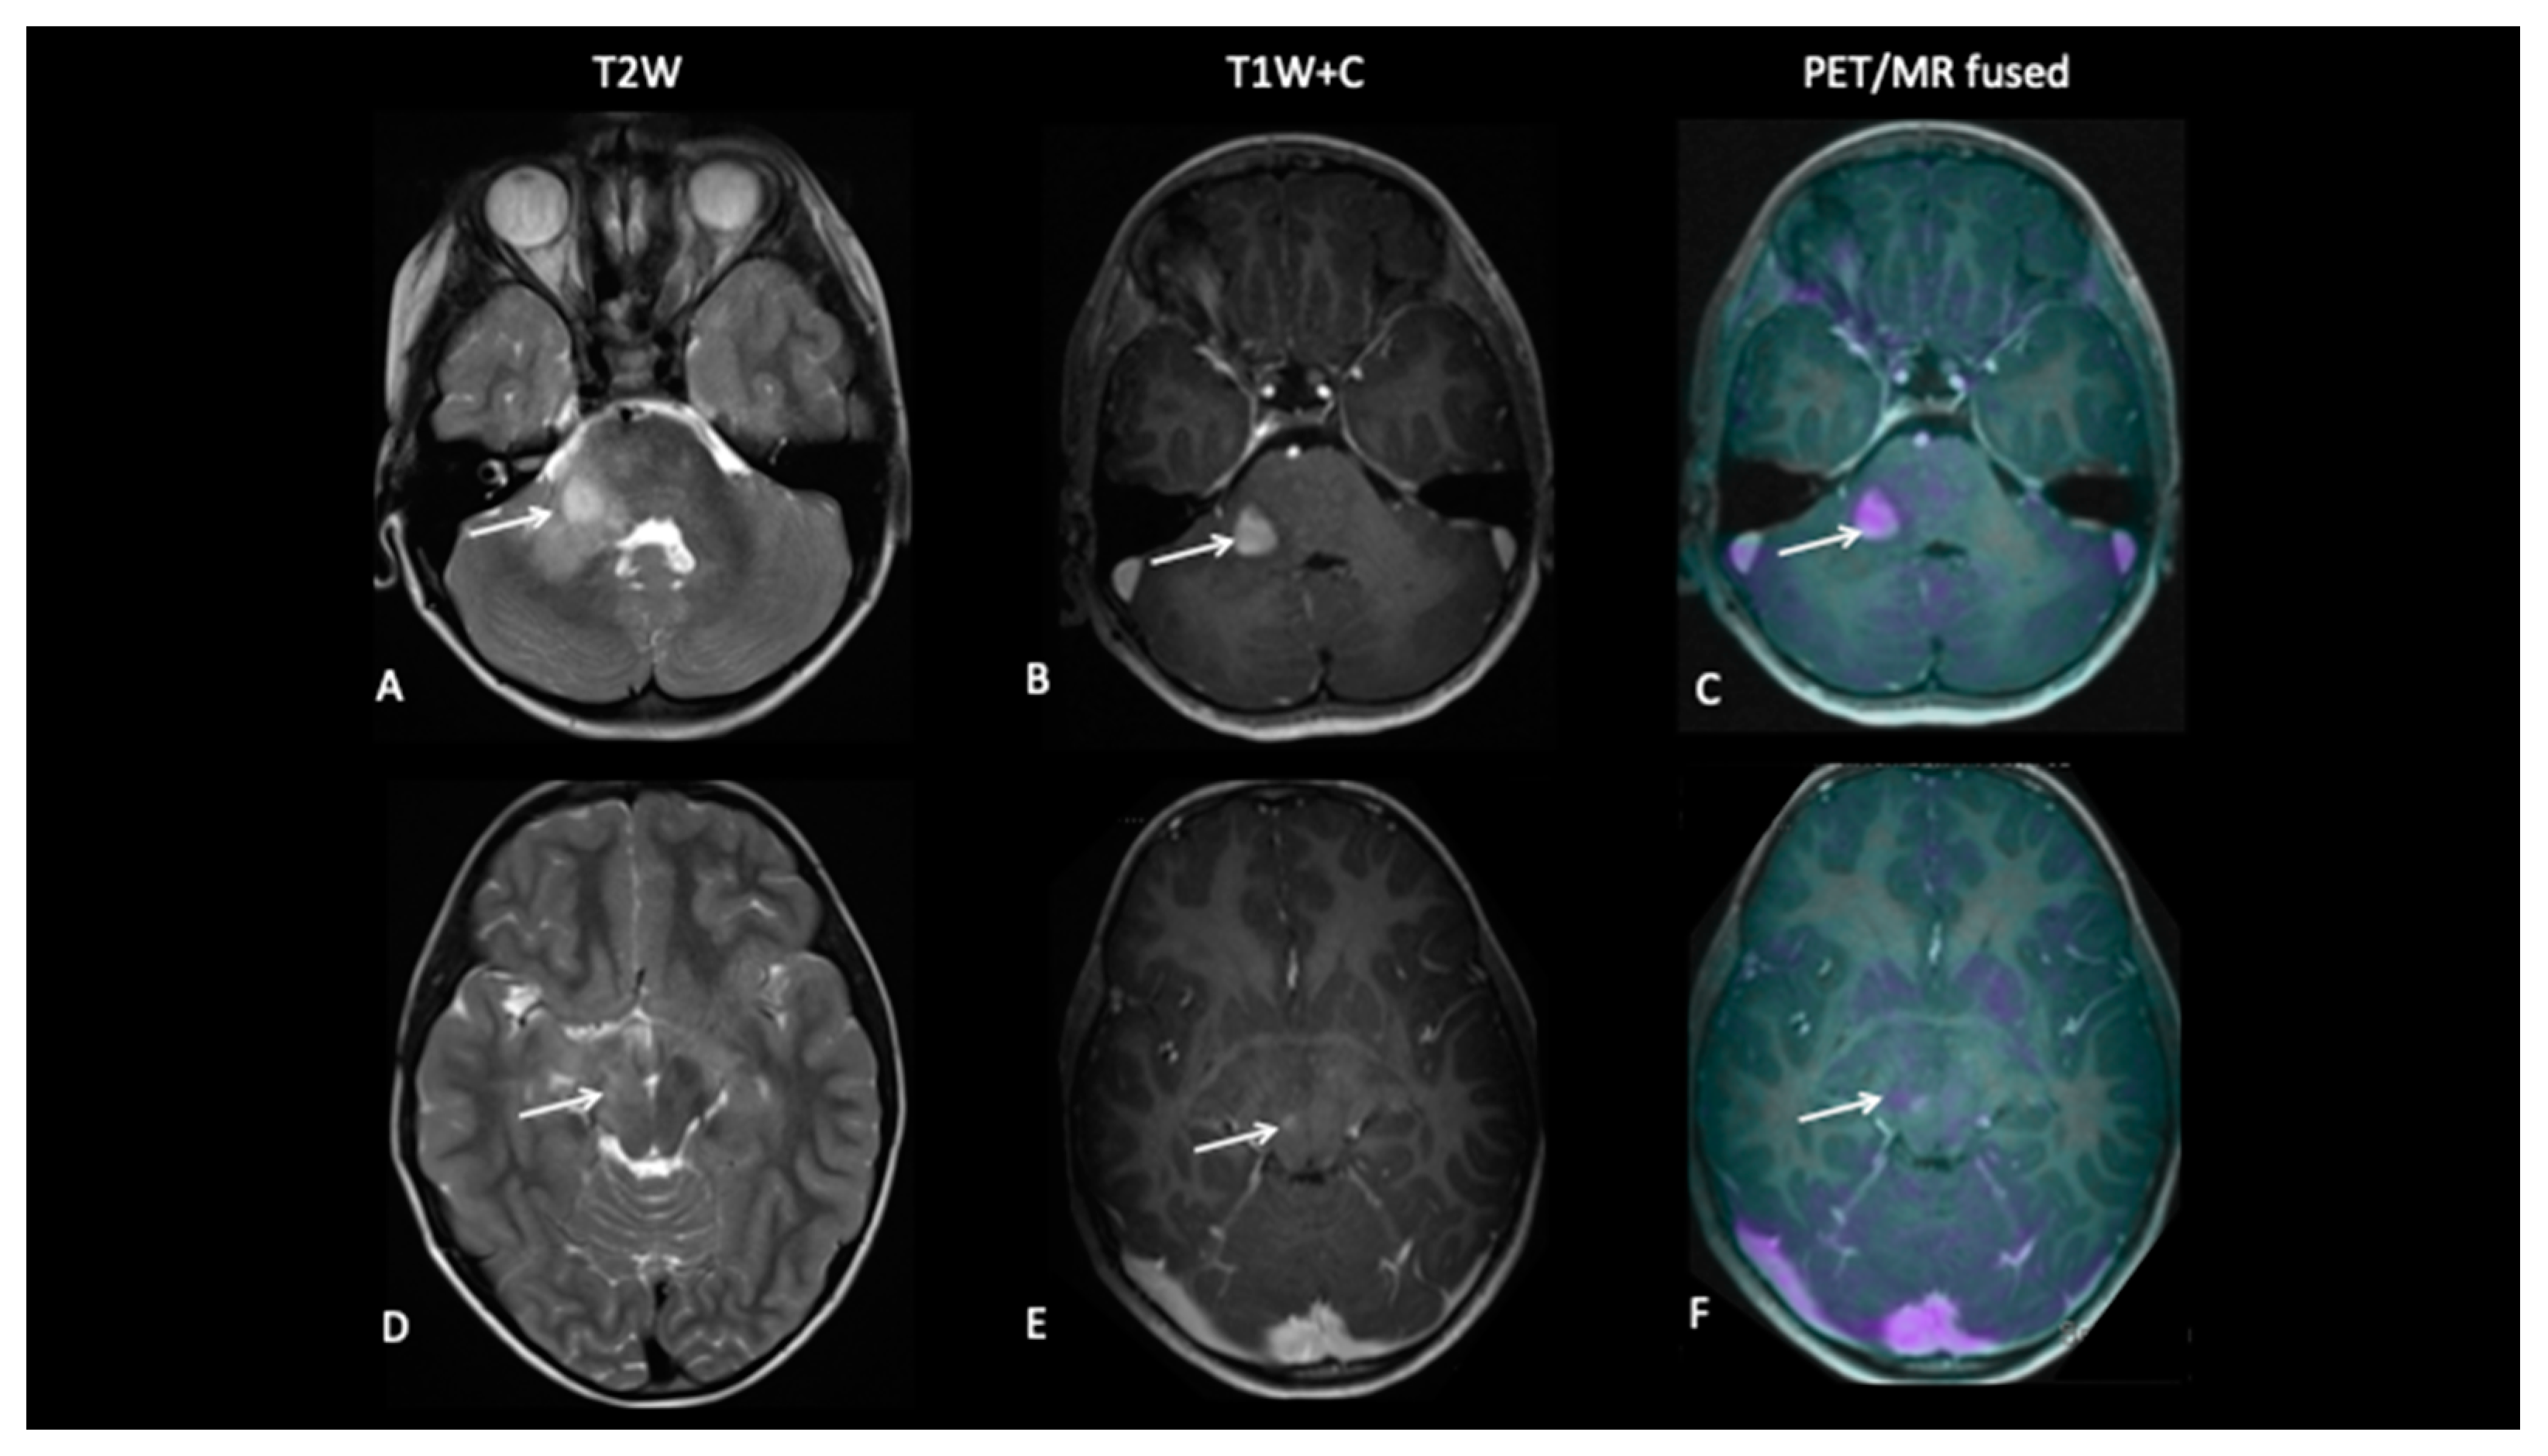

A 15-year-old male with a large tumour involving the left thalamus underwent gross resection of the thalamic tumour, and the histology confirmed this to be a high-grade astrocytoma with the known histone H3F3A K27M mutation. A response assessment scan after 6 months of chemotherapy (Figure 7) suggested minimal enhancement in the residual tumour that was thought to be pseudoprogression. However, FDOPA showed tracer uptake consistent with tumour progression.

Figure 7.

The baseline imaging post-surgery demonstrates residual non-enhancing tumour in the medial right thalamus (A–C). Follow-up imaging demonstrates the non-enhancing component (D) and mild enhancement of this component (E), uncertain for tumour progression or pseudoprogression, but the FDOPA (F) demonstrates increased uptake consistent with tumour progression.